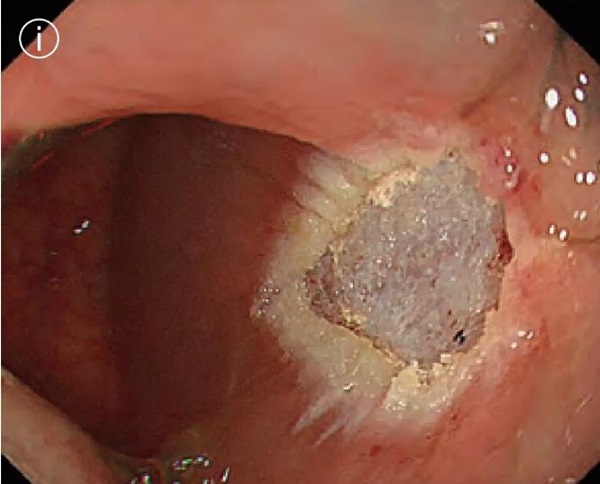

i. Power on removal

No perforation, bleeding or residual tumor was found.